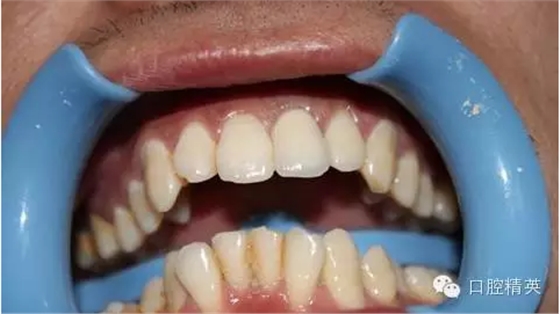

7:試戴烤瓷牙,鈷鉻瓷牙,瓷肩臺處理

8:頸緣檢查

9:完全就位

10:黏結(jié)后,側(cè)面觀

術前 ↑

術后 ↓

11:正面微笑圖